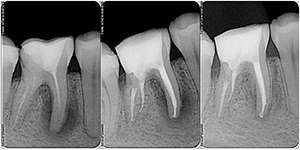

Прицельный снимок зуба – это рентгенологическая диагностика одного зуба или мини-группы (до четырех зубов). Состояние тканей – дентина и костной, десны, каналов, корня и прилегающих сосудов – вот область исследования, проводимого при помощи этого метода. Он позволяет поставить точный диагноз, получив полное представление о состоянии всех важных составляющих зуба, назначить верное лечении, а также контролировать его прохождение и результативность, корректировать при необходимости.

Прицельный снимок зубов – это инструмент, который позволяет не только подтвердить предполагаемый диагноз, но и выявить скрытые заболевания, те, которые невозможно увидеть при обыкновенном осмотре. Например, развитие кариеса на ранней стадии, или различные поражения тканей, болезни пародонта и прочие. Контроль результатов проведенного лечения при помощи этого метода также становится в разы проще и эффективнее. Уже после, допустим, пломбирования или депульпирования, врач видит результаты своих трудов. Стоит ли говорить, что все это почти на 100% защищает пациента от осложнений и исправлений лечения.